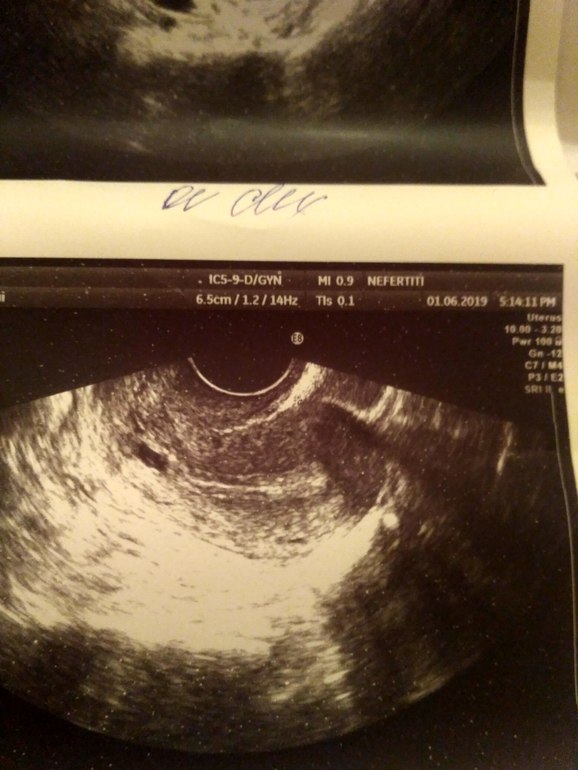

вот такая картина в матке...но она ни чего не сказала,смущает чёрное пятнышко,раньше не было

На фото яичник или матка? Если матка, то это похоже на плодное яйцо, если яичник, то киста желтого тела, которая вполне нормальна при беременности.

В общем: в яичнике -желтое тело, по размерам вполне хорошее. В матке плодное яйцо-по размерам недели 2 от зачатия. Если бластоцилла смогла внедрится в эндометрий 6,5-значит ее это устроило. Суть не всегда в толщине-главное однородность. А однородность слоя хорошая, т.к. иных включений кроме темного пятнышка я не вижу.

Любой нормальный врач должен был хотя бы сделать предположение, что это за включение в матке, т.к. в норме там вообще ничего не должно быть, от слова СОВСЕМ. Что может быть в матке:

очаги аденомиоза, но это выглядит совсем иначе, это россыпь темных пятен разного размера.

Полип или миома, но это не за один день появляется (и не за пару недель) и на предыдущих узи они бы тоже были.

Учитывая наличие ЖТ, тест и включение в матке это беременность малого срока!

Вам на хгч, смотреть динамику. И лучше через недели 2 сходить еще на узи. Узнать какой в вашем городе лучший специалист (такие обычно нет-нет, но в любом городе имеются) и сразу записаться (обычно к таким запись как раз за 2 недели или огромные очереди). Если вдруг (чего я совсем не желаю) пройдут месячные, обязательно после этого сходить на узи и посмотреть есть включение в матке или нет, чтобы исключить полип или миому. Но опять же, по картине на сегодняшний день это не они.

вот это матка что то вижу,она ни чего не сказала